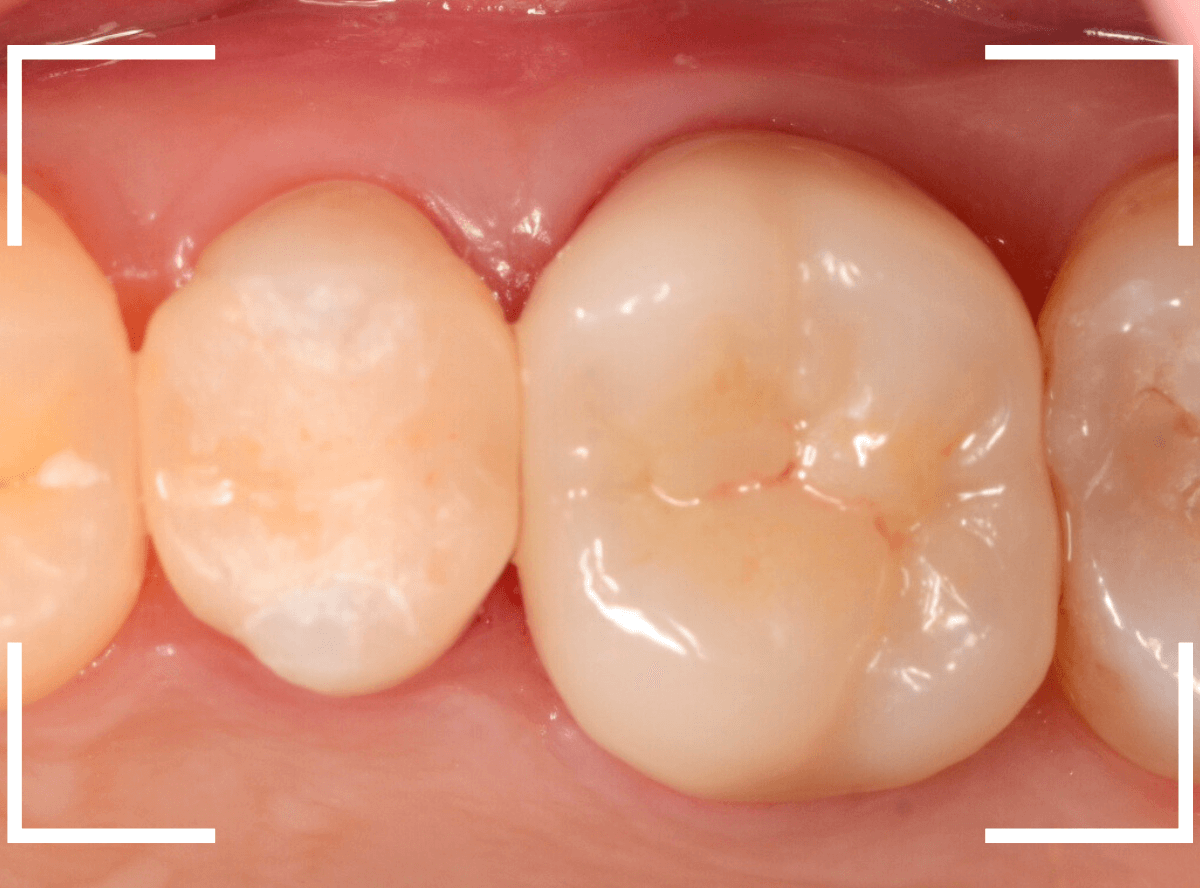

set後の写真です。

患者さんにも満足していただける仕上がりになりました。

治療前後の比較写真になります。